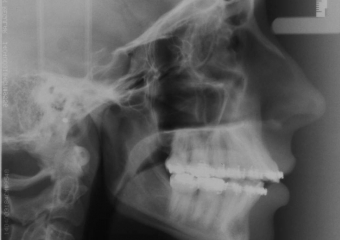

Teleradiografia final